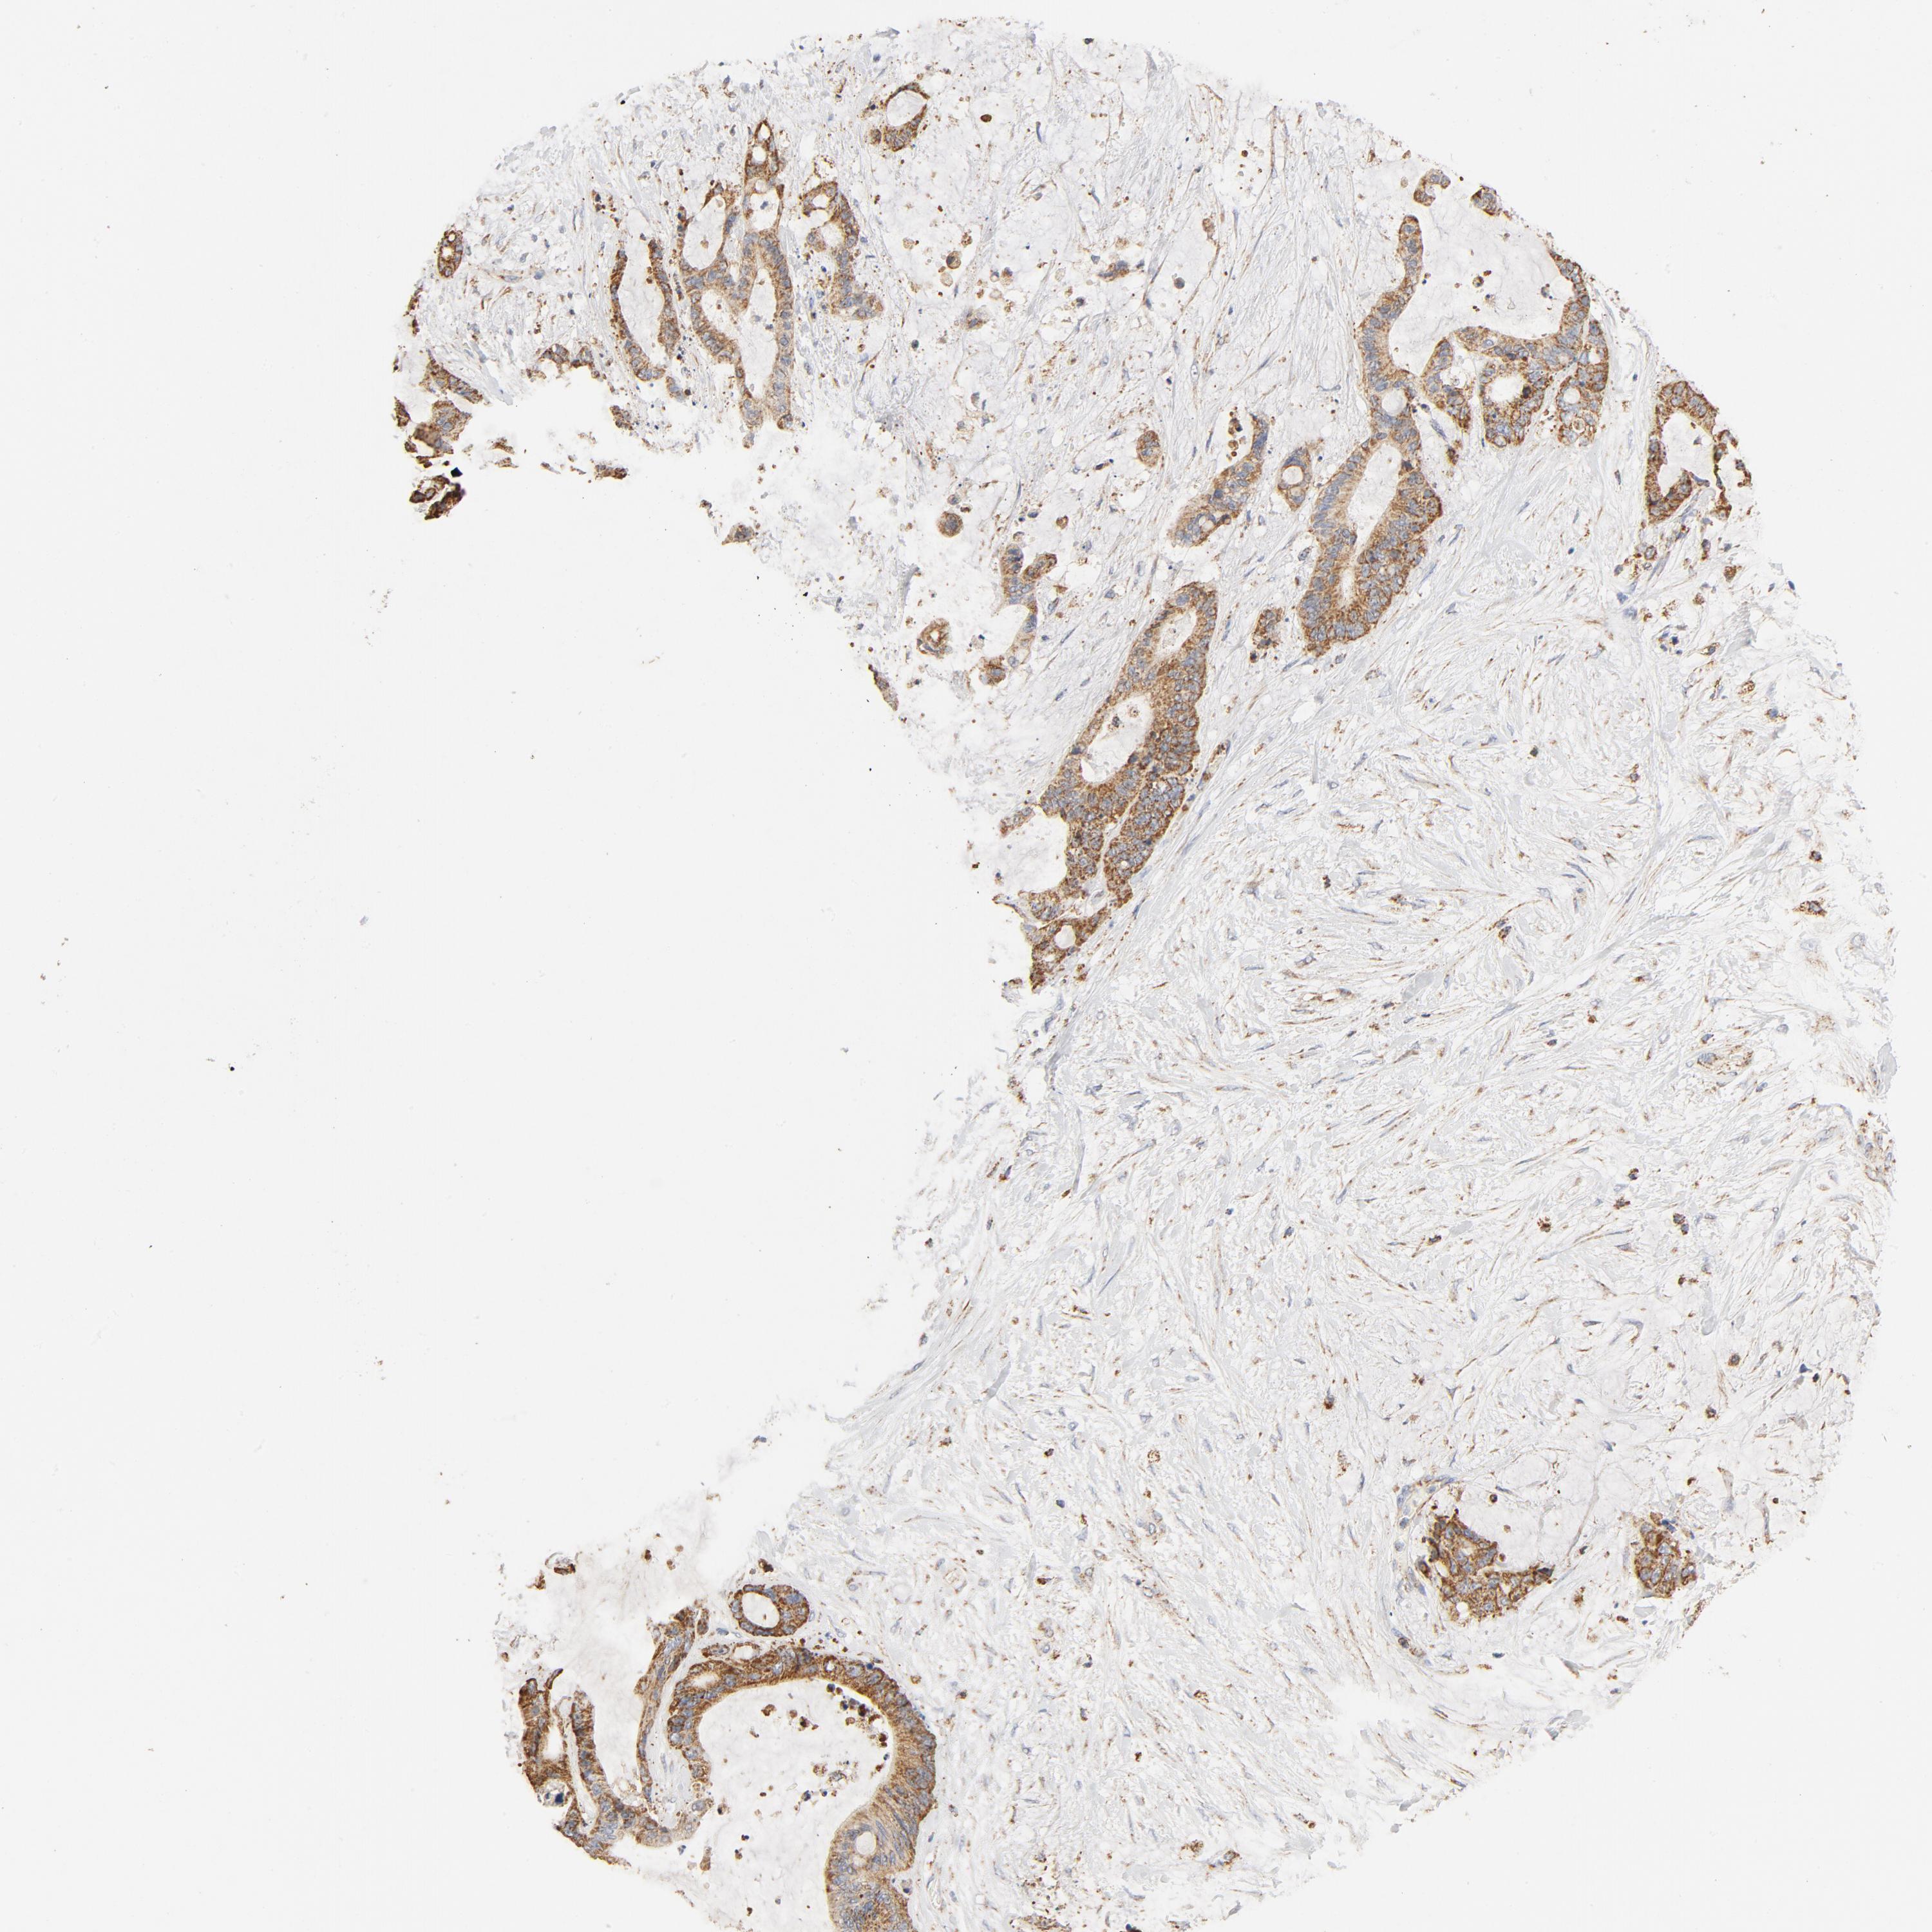

LIVER CANCER - Protein expressioni

A mouse-over function shows sample information and annotation data. Click on an image to view it in a full screen mode. Samples can be filtered based on level of antibody staining by selecting one or several of the following categories: high, medium, low and not detected. The assay and annotation is described here.

Note that samples used for immunohistochemistry by the Human Protein Atlas do not correspond to samples in the TCGA dataset.

Antibody stainingi

Antibody staining in the annotated cell types in the current human tissue is reported as not detected, low, medium, or high, based on conventional immunohistochemistry profiling in selected tissues. This score is based on the combination of the staining intensity and fraction of stained cells.

Each image is clickable and will lead to virtual microscopy that enables deeper exploration of all samples and also displays staining intensity scores, fraction scores and subcellular localization as well as patient and tissue information for each sample.

Antibody HPA002485

Antibody CAB004080

Staining

High

Medium

Low

Not detected

Intensity

Strong

Moderate

Weak

Negative

Quantity

>75%

75%-25%

<25%

None

Location

Nuclear

Cytoplasmic/membranous

Cytoplasmic/membranous,nuclear

Cholangiocarcinoma

Carcinoma, Hepatocellular, NOS